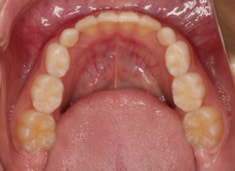

検査時のレントゲン分析では、上下顎の関係は、上顎の劣成長があり下顎前突傾向という値がでておりましたが、前歯ジャンプ後はフェイスマスクの効果もあり、上下顎の関係は正常化しています。

上顎が若干優位になっていますので、今後の下顎の成長のための貯金になっているくらいです。